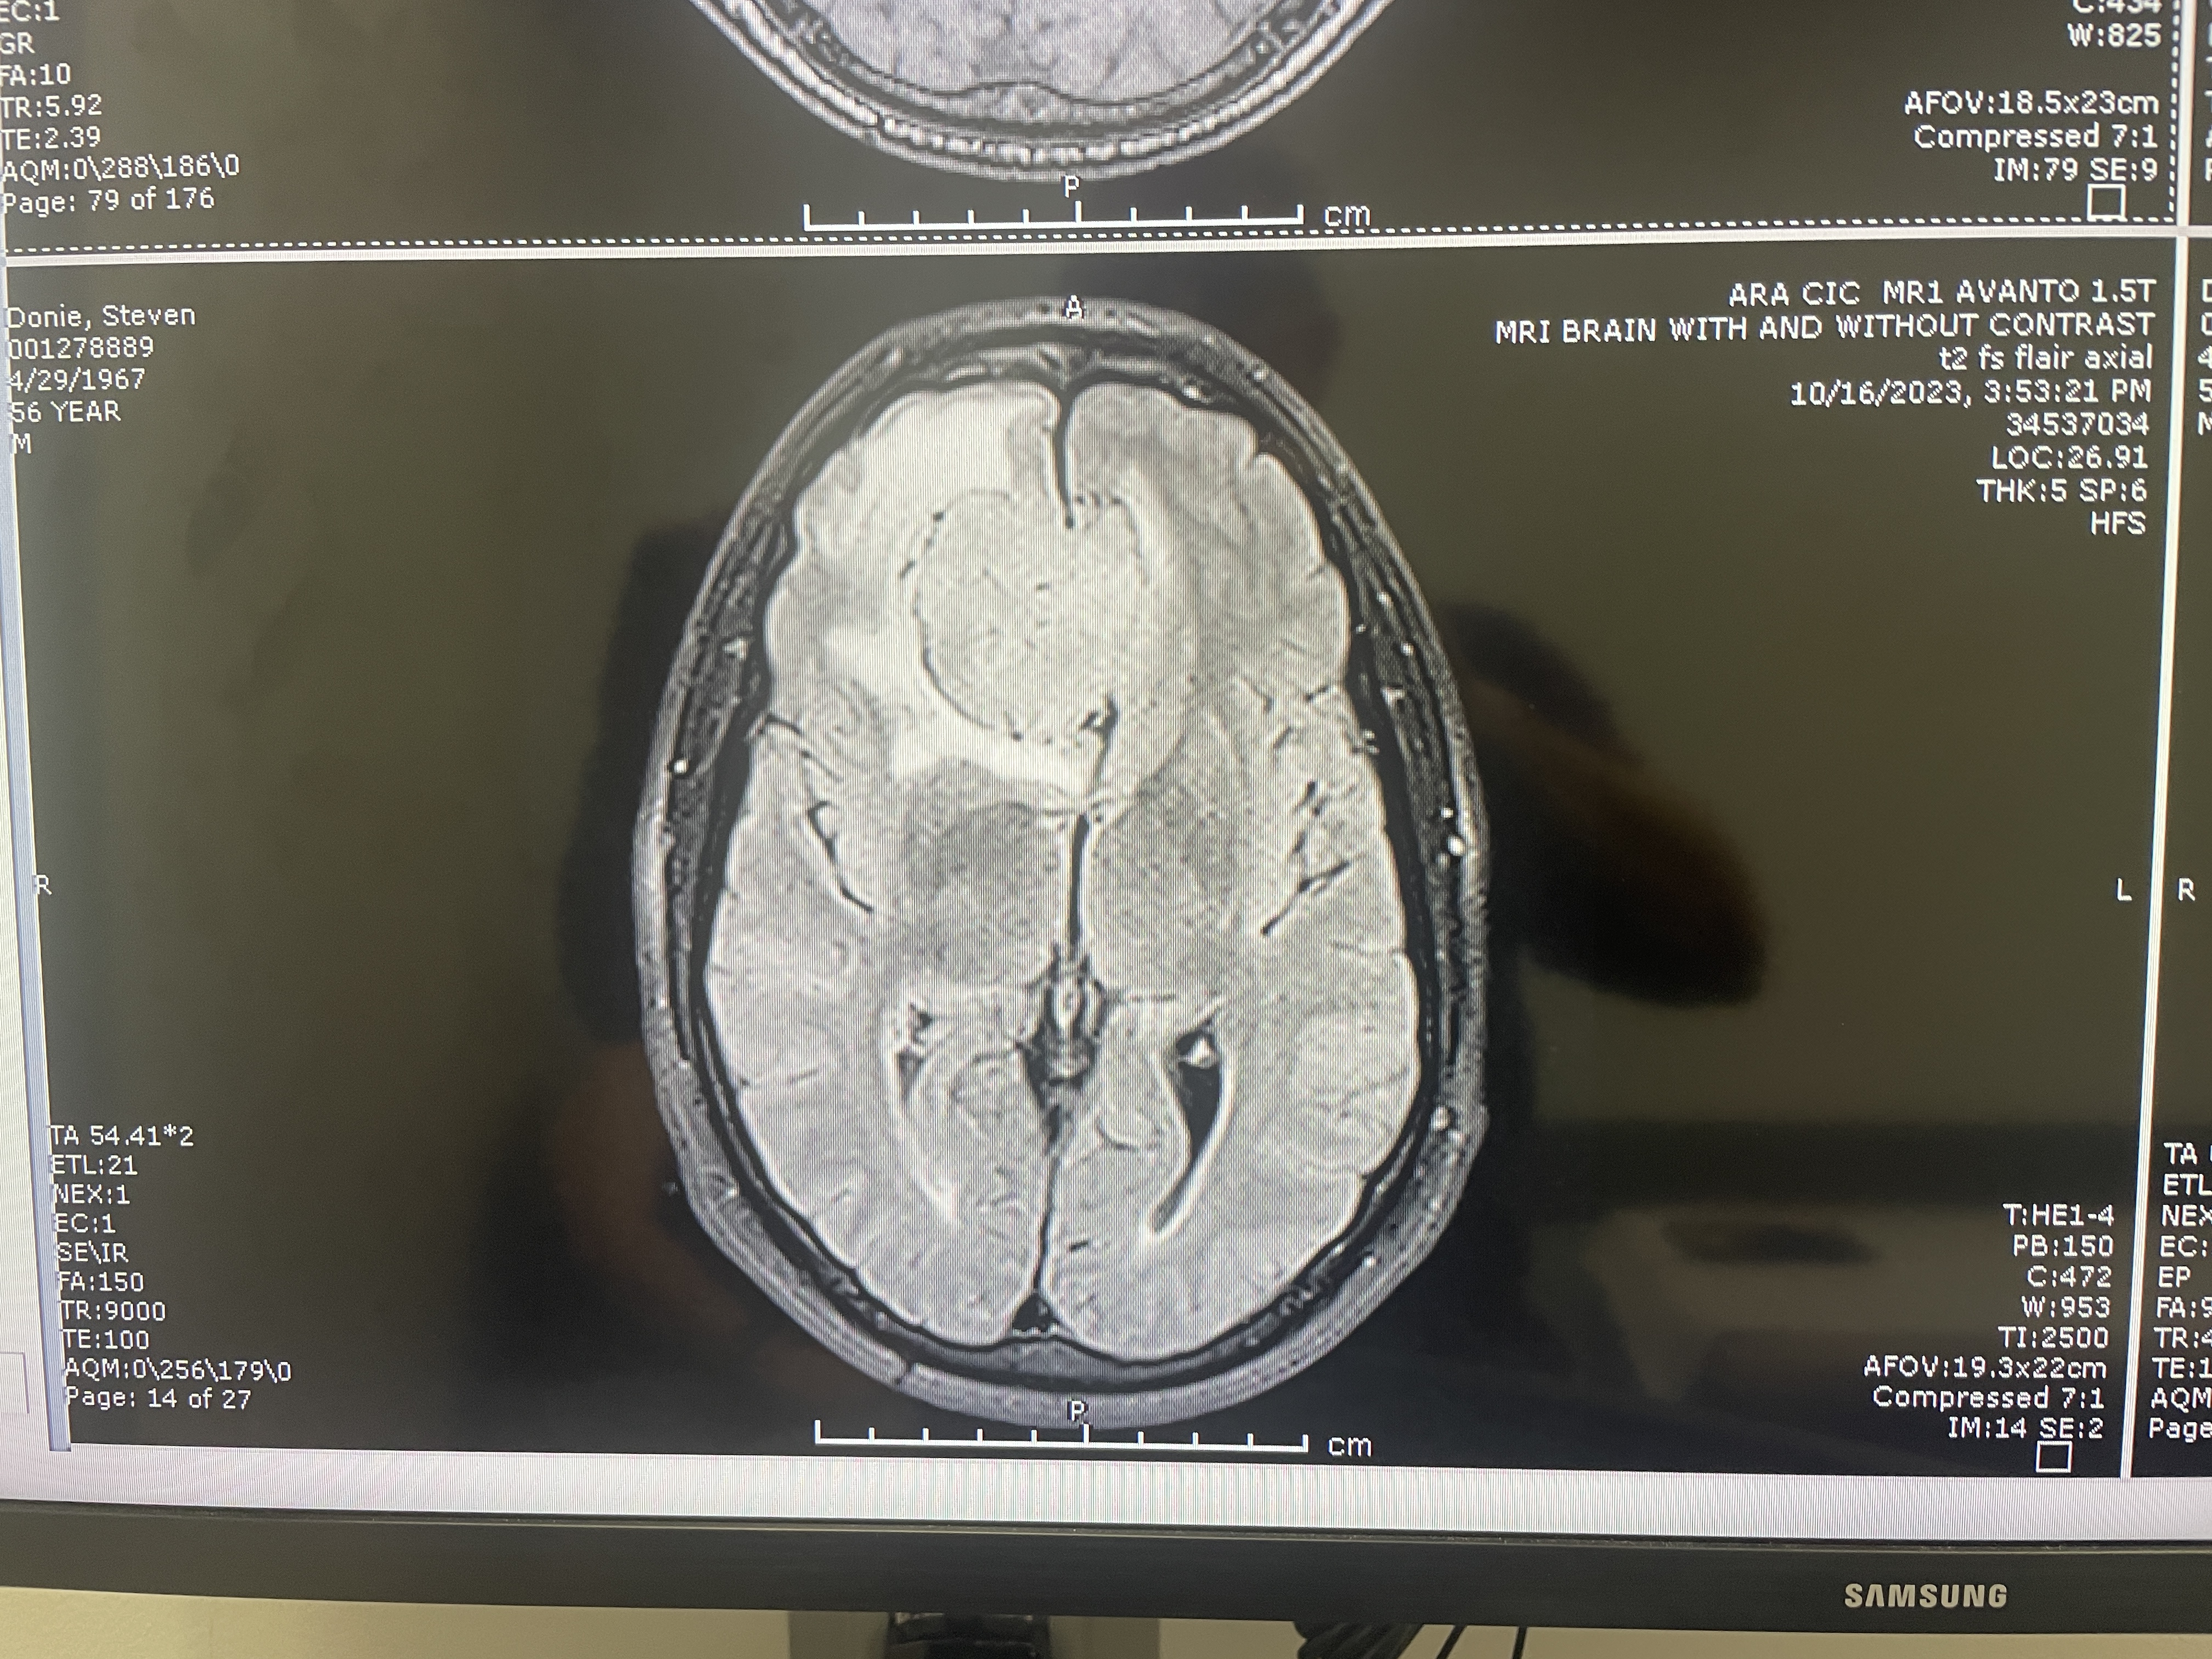

MRI, top view